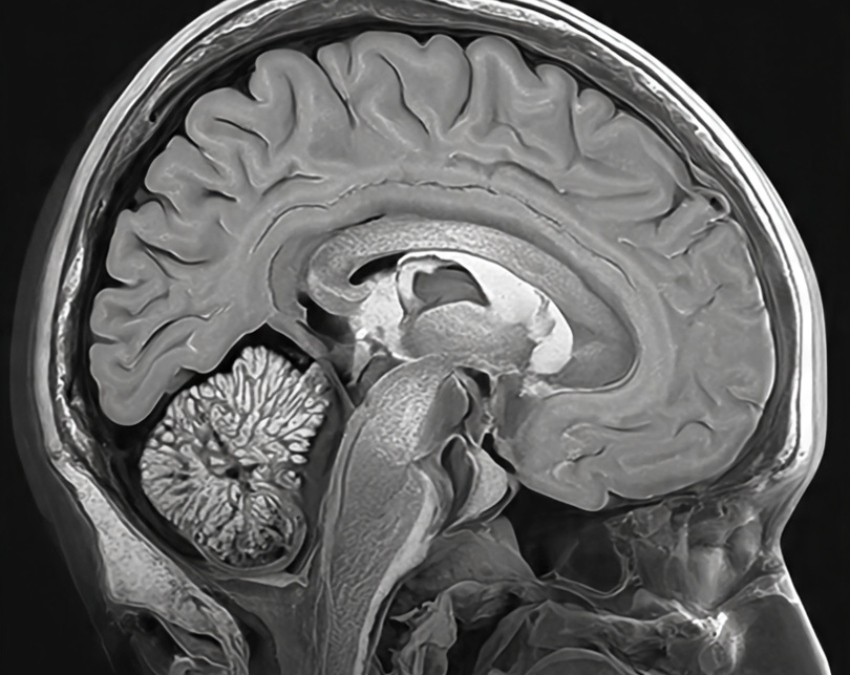

क्या होता है ब्रेन ट्यूमर?

इस गंभीर समस्या को लेकर एक्सपर्ट्स बताते हैं कि, ब्रेन ट्यूमर दिमाग की कोशिकाओं के डीएनए में होने वाली बदलाव या तो कोशिकाएं सामान्य नियंत्रण खो देने से यह कोशिकाएं अनियंत्रित तरीके से बढ़ने लगती है. इसी असामान्य वृद्धि के कारण ब्रेन ट्यूमर बनने लगता है.